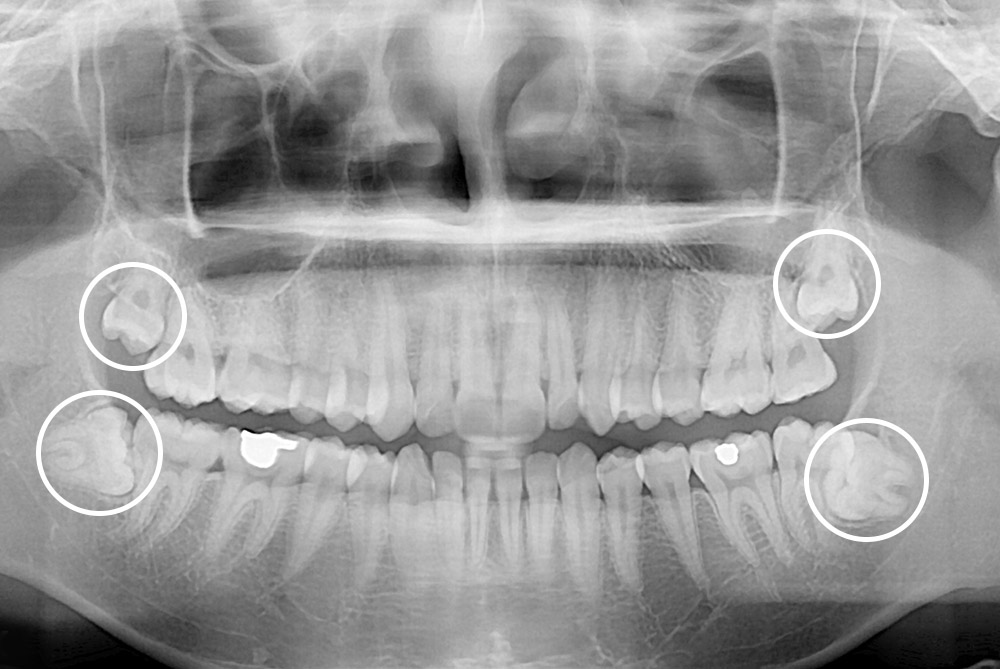

[사랑니] 매복 사랑니 발치

치료전 : 2018-08-16